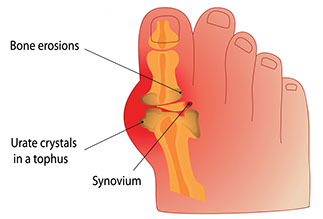

Gout

Signs & Symptoms

Severe pain in foot joint, often the big toe. The pain is not due to an injury. The joint hurts a lot when anything touches it. The area is red, swollen, and tender.

What to Do

See doctor.